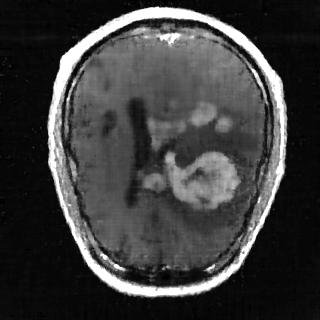

This article presents a novel undersampled magnetic resonance imaging (MRI) technique that leverages the concept of Neural Radiance Field (NeRF). With radial undersampling, the corresponding imaging problem can be reformulated into an image modeling task from sparse-view rendered data; therefore, a high dimensional MR image is obtainable from undersampled $k$-space data by taking advantage of implicit neural representation. A multi-layer perceptron, which is designed to output an image intensity from a spatial coordinate, learns the MR physics-driven rendering relation between given measurement data and desired image. Effective undersampling strategies for high-quality neural representation are investigated. The proposed method serves two benefits: (i) The learning is based fully on single undersampled $k$-space data, not a bunch of measured data and target image sets. It can be used potentially for diagnostic MR imaging, such as fetal MRI, where data acquisition is relatively rare or limited against diversity of clinical images while undersampled reconstruction is highly demanded. (ii) A reconstructed MR image is a scan-specific representation highly adaptive to the given $k$-space measurement. Numerous experiments validate the feasibility and capability of the proposed approach.